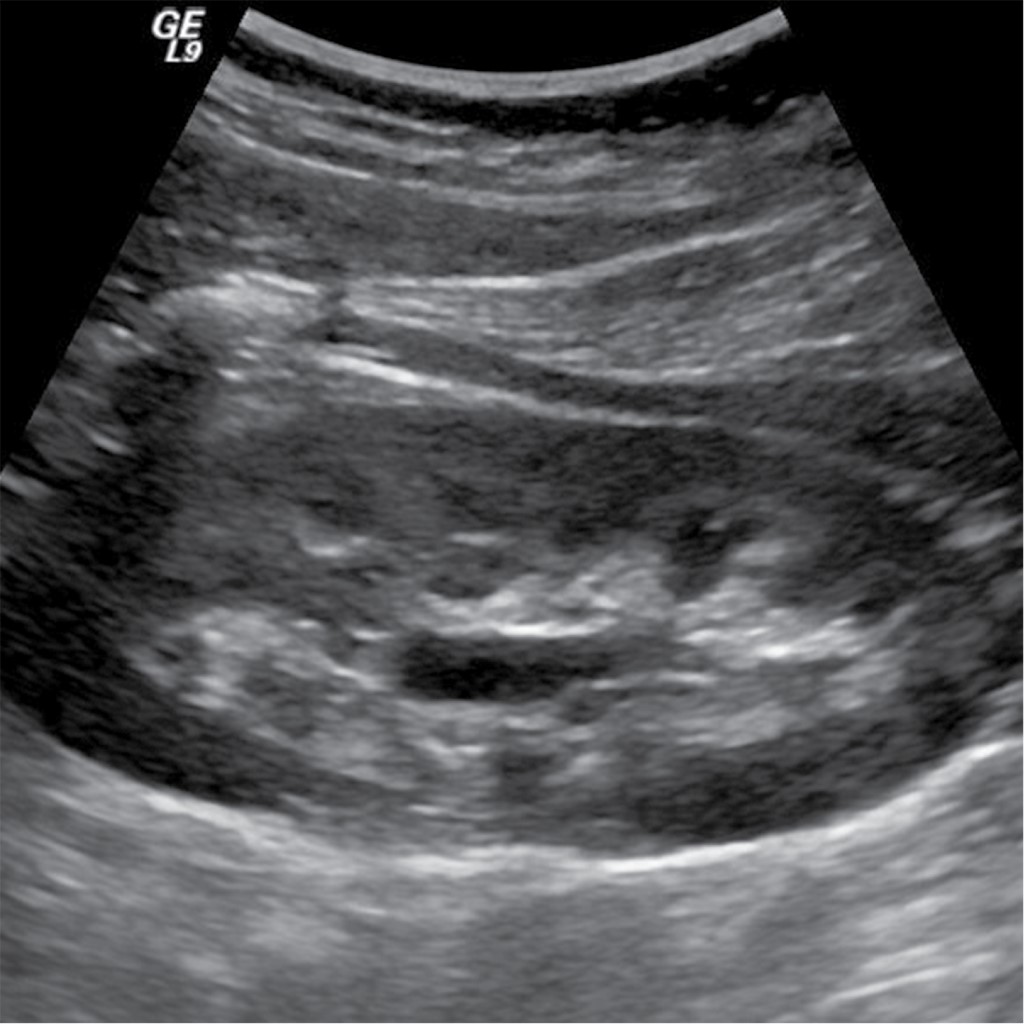

En el ultrasonido renal se observan ambos riñones de tamaño normal, con pérdida de la relación córtico-medular, con pirámides francamente ecogénicas en relación a nefrocalcinosis bilateral, sin evidencia de dilatación de los sistemas colectores (Figura 3).

Ultrasonido renal muestra en riñón izquierdo dilatación pielocalicial con imágenes ecogénicas en pirámides sugestivas de nefrocalcinosis (Figura 8).

El caso 1 inicialmente tuvo insuficiencia renal aguda, que remitió sin terapia de reemplazo renal, ya que no tuvo criterios para diálisis. Además, se comprobó hipercalciuria hipercalcémica y supresión de la hormona paratiroidea como ocurrió en el caso 1 y el 2 acompañada de disminución de la reabsorción tubular de fosfatos, que condicionó nefrocalcinosis (Figuras 3 y 8).